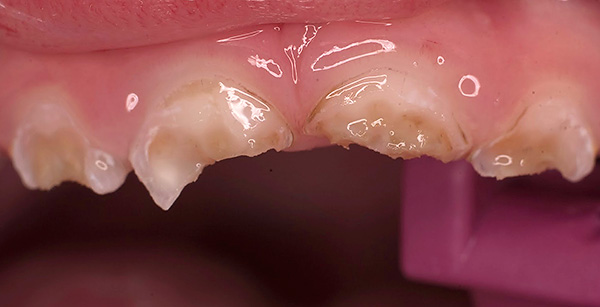

Às vezes, existe um conceito absolutamente errado dos pais de que, como os dentes de leite são temporários, você não precisa cuidar deles. Eles dizem que vão cair de qualquer maneira, e então já será possível fazer uma higiene mais completa. Com essa abordagem, a condição dos dentes do bebê em um bebê pode ser verdadeiramente catastrófica:

É importante entender que problemas na mordida do leite inevitavelmente terão um efeito prejudicial na mordida permanente e, às vezes (mesmo com processos inflamatórios graves), até os rudimentos de futuros dentes permanentes podem ser danificados.